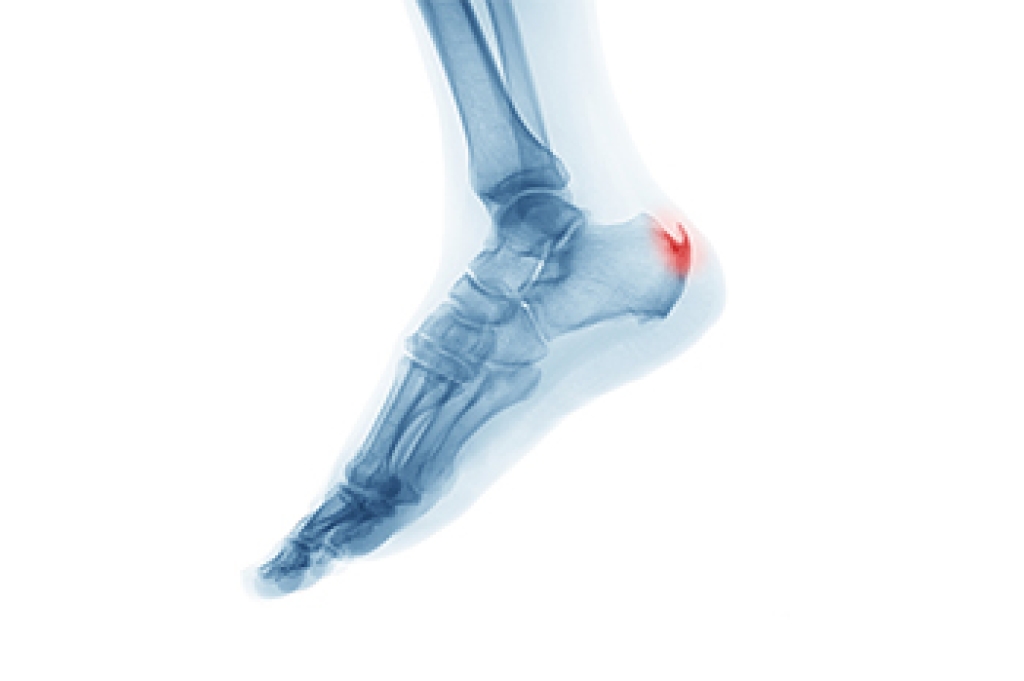

Heel spurs are formed by calcium deposits on the back of the foot where the heel is. This can also be caused by small fragments of bone breaking off one section of the foot, attaching onto the back of the foot. Heel spurs can also be bone growth on the back of the foot and may grow in the direction of the arch of the foot.

The pain associated with spurs is often because of weight placed on the feet. When someone is walking, their entire weight is concentrated on the feet. Bone spurs then have the tendency to affect other bones and tissues around the foot. As the pain continues, the feet will become tender and sensitive over time.